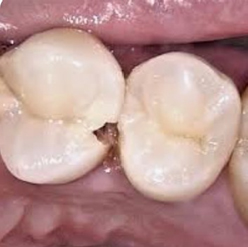

• C2:象牙質に達するう蝕

エナメル質の内側の象牙質にまで達するう蝕です。

象牙質は歯の中の神経(歯髄組織)と関わっており、症状としては、冷たいものがしみたり、粘着性にある甘いもの(キャラメルやチョコレートなど)を食べると痛みが出たりします。

う蝕除去時に痛みを伴うことがあるため、必要に応じて局所麻酔を行うことがあります。

〈治療法〉

う蝕の範囲が狭い場合はう蝕を除去し、コンポジットレジン充填を行います。

範囲が広かったり、歯と歯の間(隣接面)にある場合は、う蝕除去後に歯型をとり、インレーと呼ばれる金属やセラミックの詰め物を作製し、修復します。